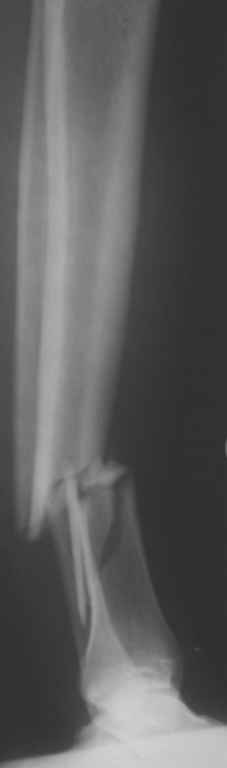

На голени что-то сделать с отломком вынуждает угроза перфорация кожи, перекрытие отломком входа в канал. Не всегда надо делать разрез, можно и шилом чрескожно фрагмент сдвинуть. Наверно, еще и повреждение сосудистого пучка, когда "виновник" прямо поперек перерезанной артерии и лежит - такое не каждый за всю свою профессиональную жизнь

встретит.

То есть в представленных ситуациях при штифтовании ни на бедре, ни на голени не нужно делать ни открытую, ни закрытую (с помощью шильев,

спиц, еще каких-то "джойстиков") репозицию. Все, что нужно - восстановить ось, длину и ротацию.

Перелом большеберцовой кости почти околосуставный, могут потребоваться дополнительные меры для восстановления оси (отклоняющие спицы или винты), и запирающих винтов в дистальный отломок желательно побольше. Задний край не сломан ли там, не разобрал по этим снимкам.

>Сами собираемся оперировать голень и думаем, что без "открытия" места перелома не обойтись.

"Открытие" "открытию" рознь. Мне видится такая последовательность действий: попытаться установить проводник закрыто на вытяжении или дистракторе. Если прошел -рассверлиться, если нет поправить направление проводника через разрез такой величины, чтобы можно это было сделать но не более того.Если осколок, стремящийся в канал свободен от мягких тканей - удалить его. Удаляли вываливающиеся отломки "перстневидной" формы по более представленного, тем не менее сращение наступало. Если удастся все провести закрыто, манипуляции с отломком нужны, если он будет стремиться перфорировать кожу.Бывает, что для этого не обязательно открываться, просто подтолкнуть осколок через кожу или (цитата:))шилом.

Общее MHO по поводу осколков:

1.мелкие не стоят внимания, если не давят на сосудисто-нервный пучок, угрожают перфорацией и т.п., и т.д.,

2.крупные, если создают дефект в области перелома, должны находиться как можно ближе к области перелома, как депо материала для костеобразования, отнюдь не должны быть точно репонированы.